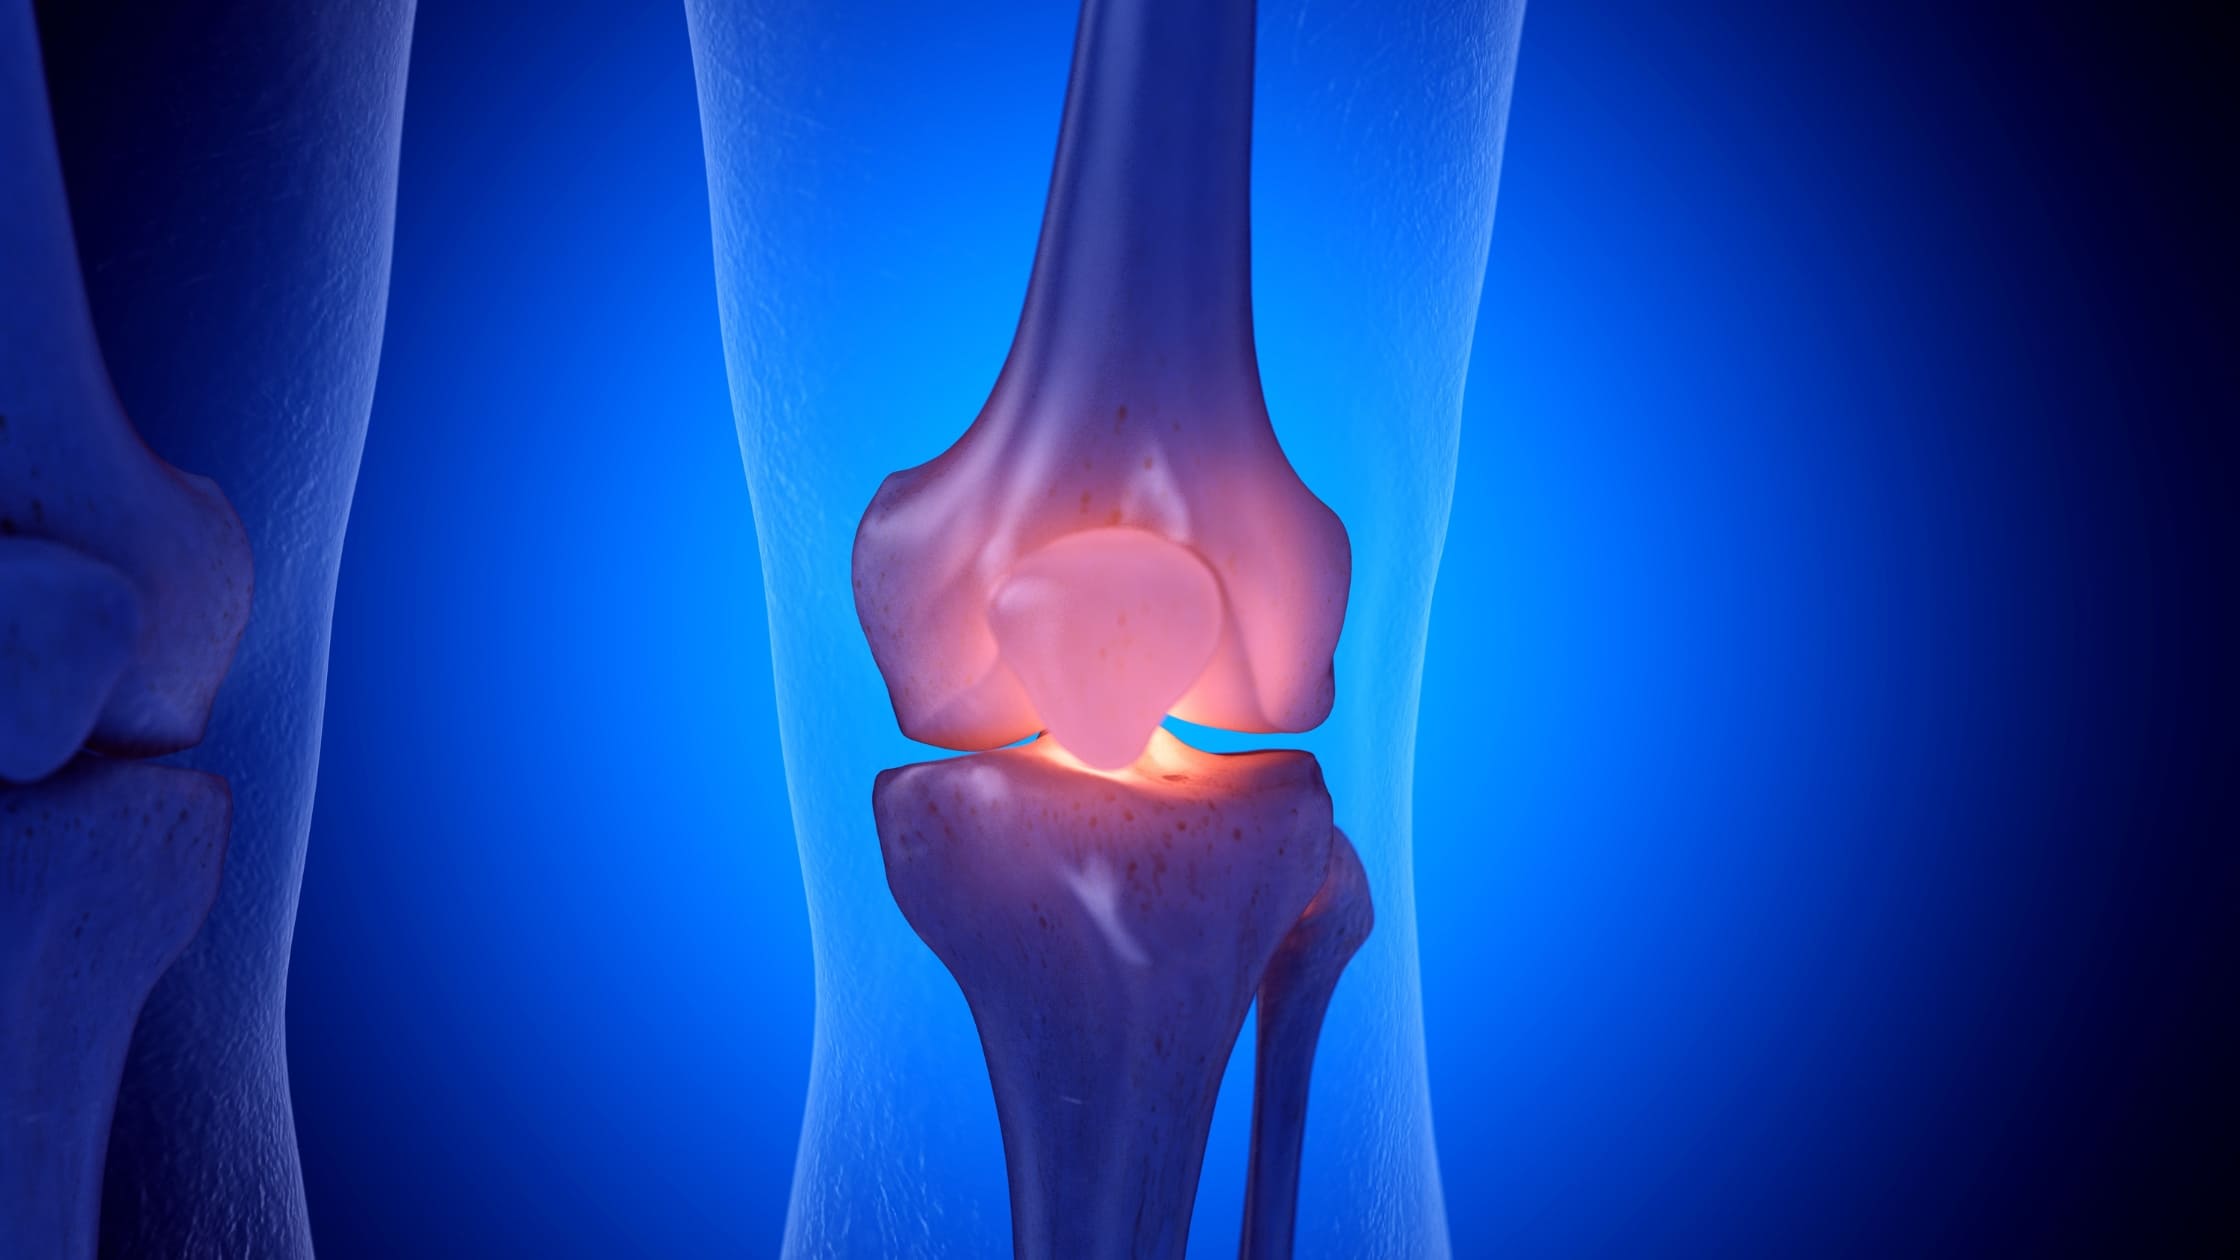

As causas mais frequentes incluem desgaste da articulação (artrose), lesões ligamentares, tendinites, problemas na cartilagem, entorses e sobrecarga por atividades físicas intensas ou repetitivas.

Entre os sintomas mais relatados estão dor localizada ou difusa, inchaço, sensação de instabilidade, rigidez, estalos e limitação para dobrar ou esticar a perna. Em alguns casos, a dor pode piorar com o esforço ou ao permanecer muito tempo parado.